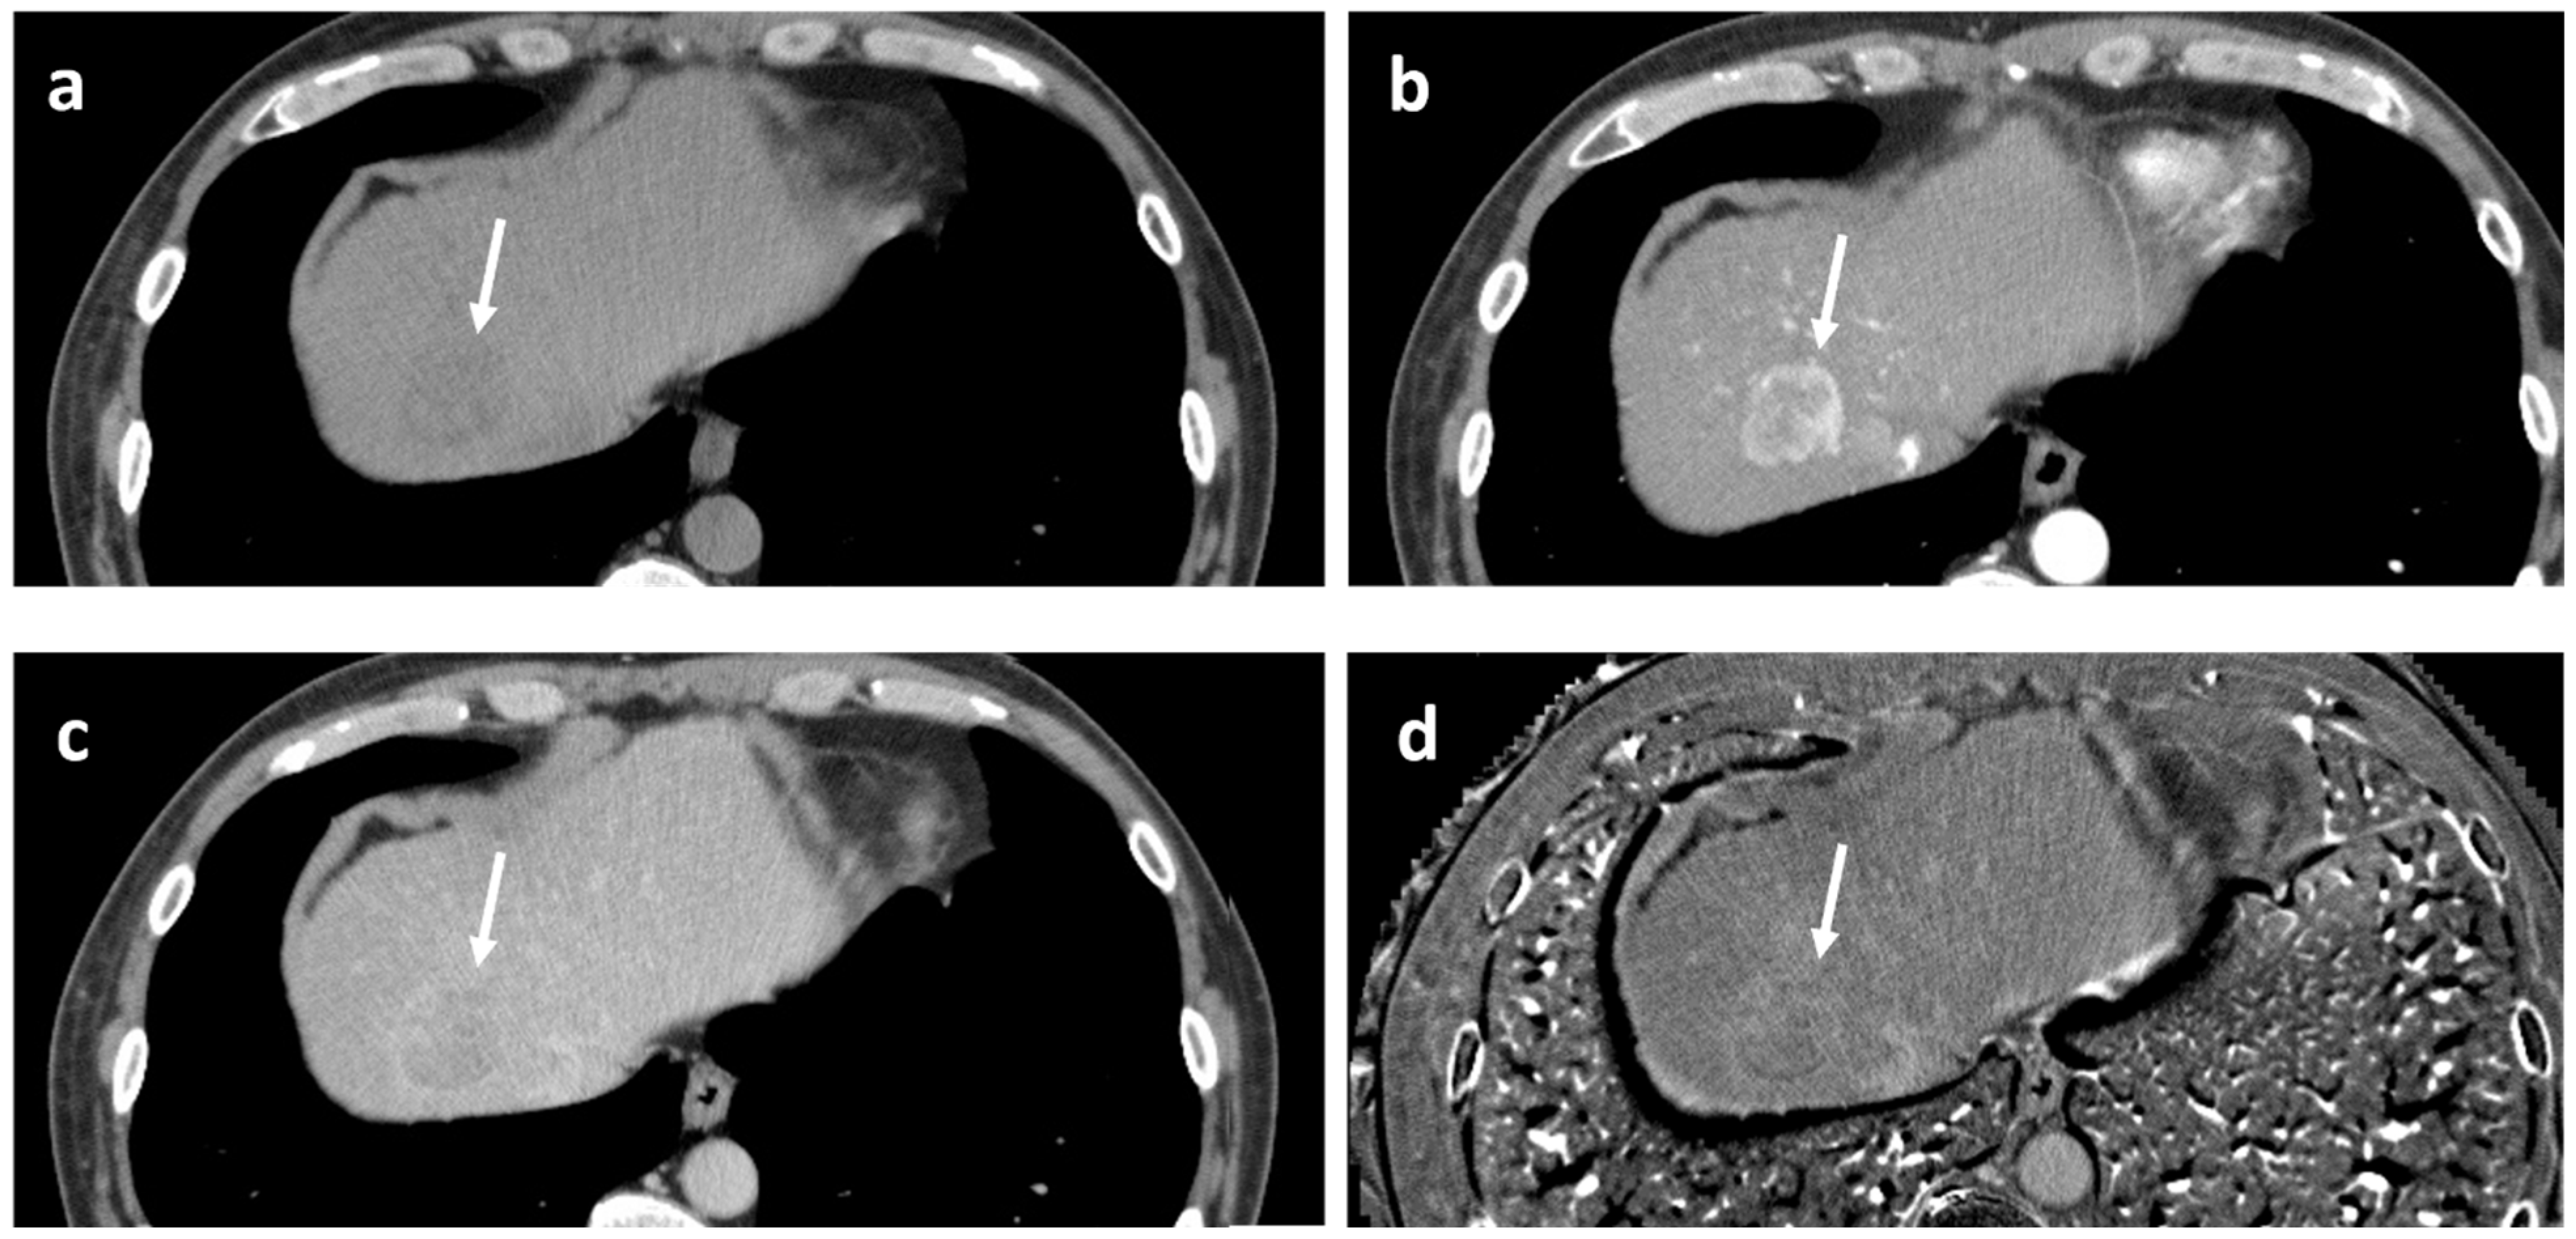

2.3. Washout at the Equilibrium Phase of CT

2.1. Washout at the PVP of CT or ECCM-MRI

2.2. Washout at the PVP of Gadoxetate-Enhanced MRI (EOB-MRI)